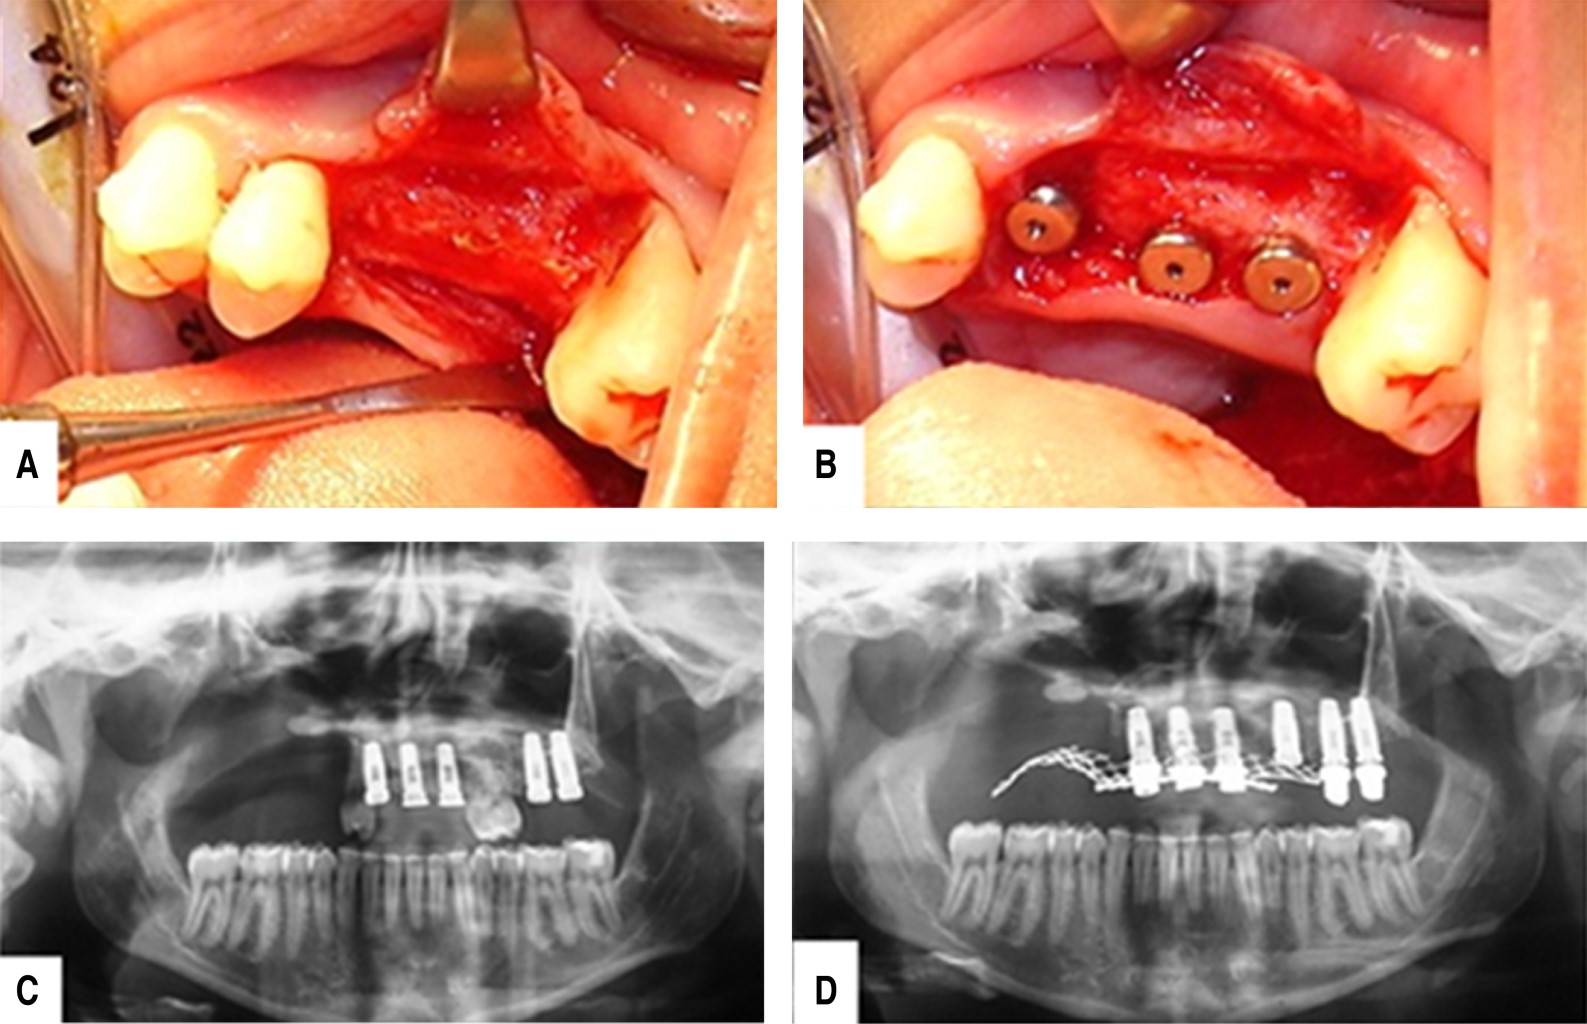

Figure 4